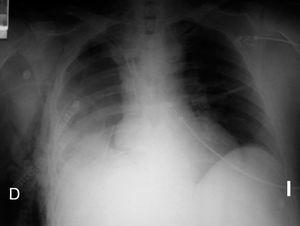

A las 24 horas del postoperatorio y tras extubar al paciente se detecta una imagen radiodensa de forma homogénea en la región inferior de hemitórax derecho (fig. 2) que hace pensar en un nuevo sangrado. En la exploración se aprecia un latido cardíaco débil en hemitórax izquierdo y mucho más intenso en lado derecho, con latido apical visible en sexto espacio intercostal derecho. En la ecocardiografía transtorácica se confirma la sospecha diagnóstica de herniación cardíaca a través de la ventana pericárdica. El paciente fue reintervenido para reintroducir los ventrículos en la cavidad pericárdica y el parche sintético fue sustituido por haber sufrido dehiscencia de suturas, lo que permitió la herniación. El paciente permaneció asintomático en todo momento.

Figura 2